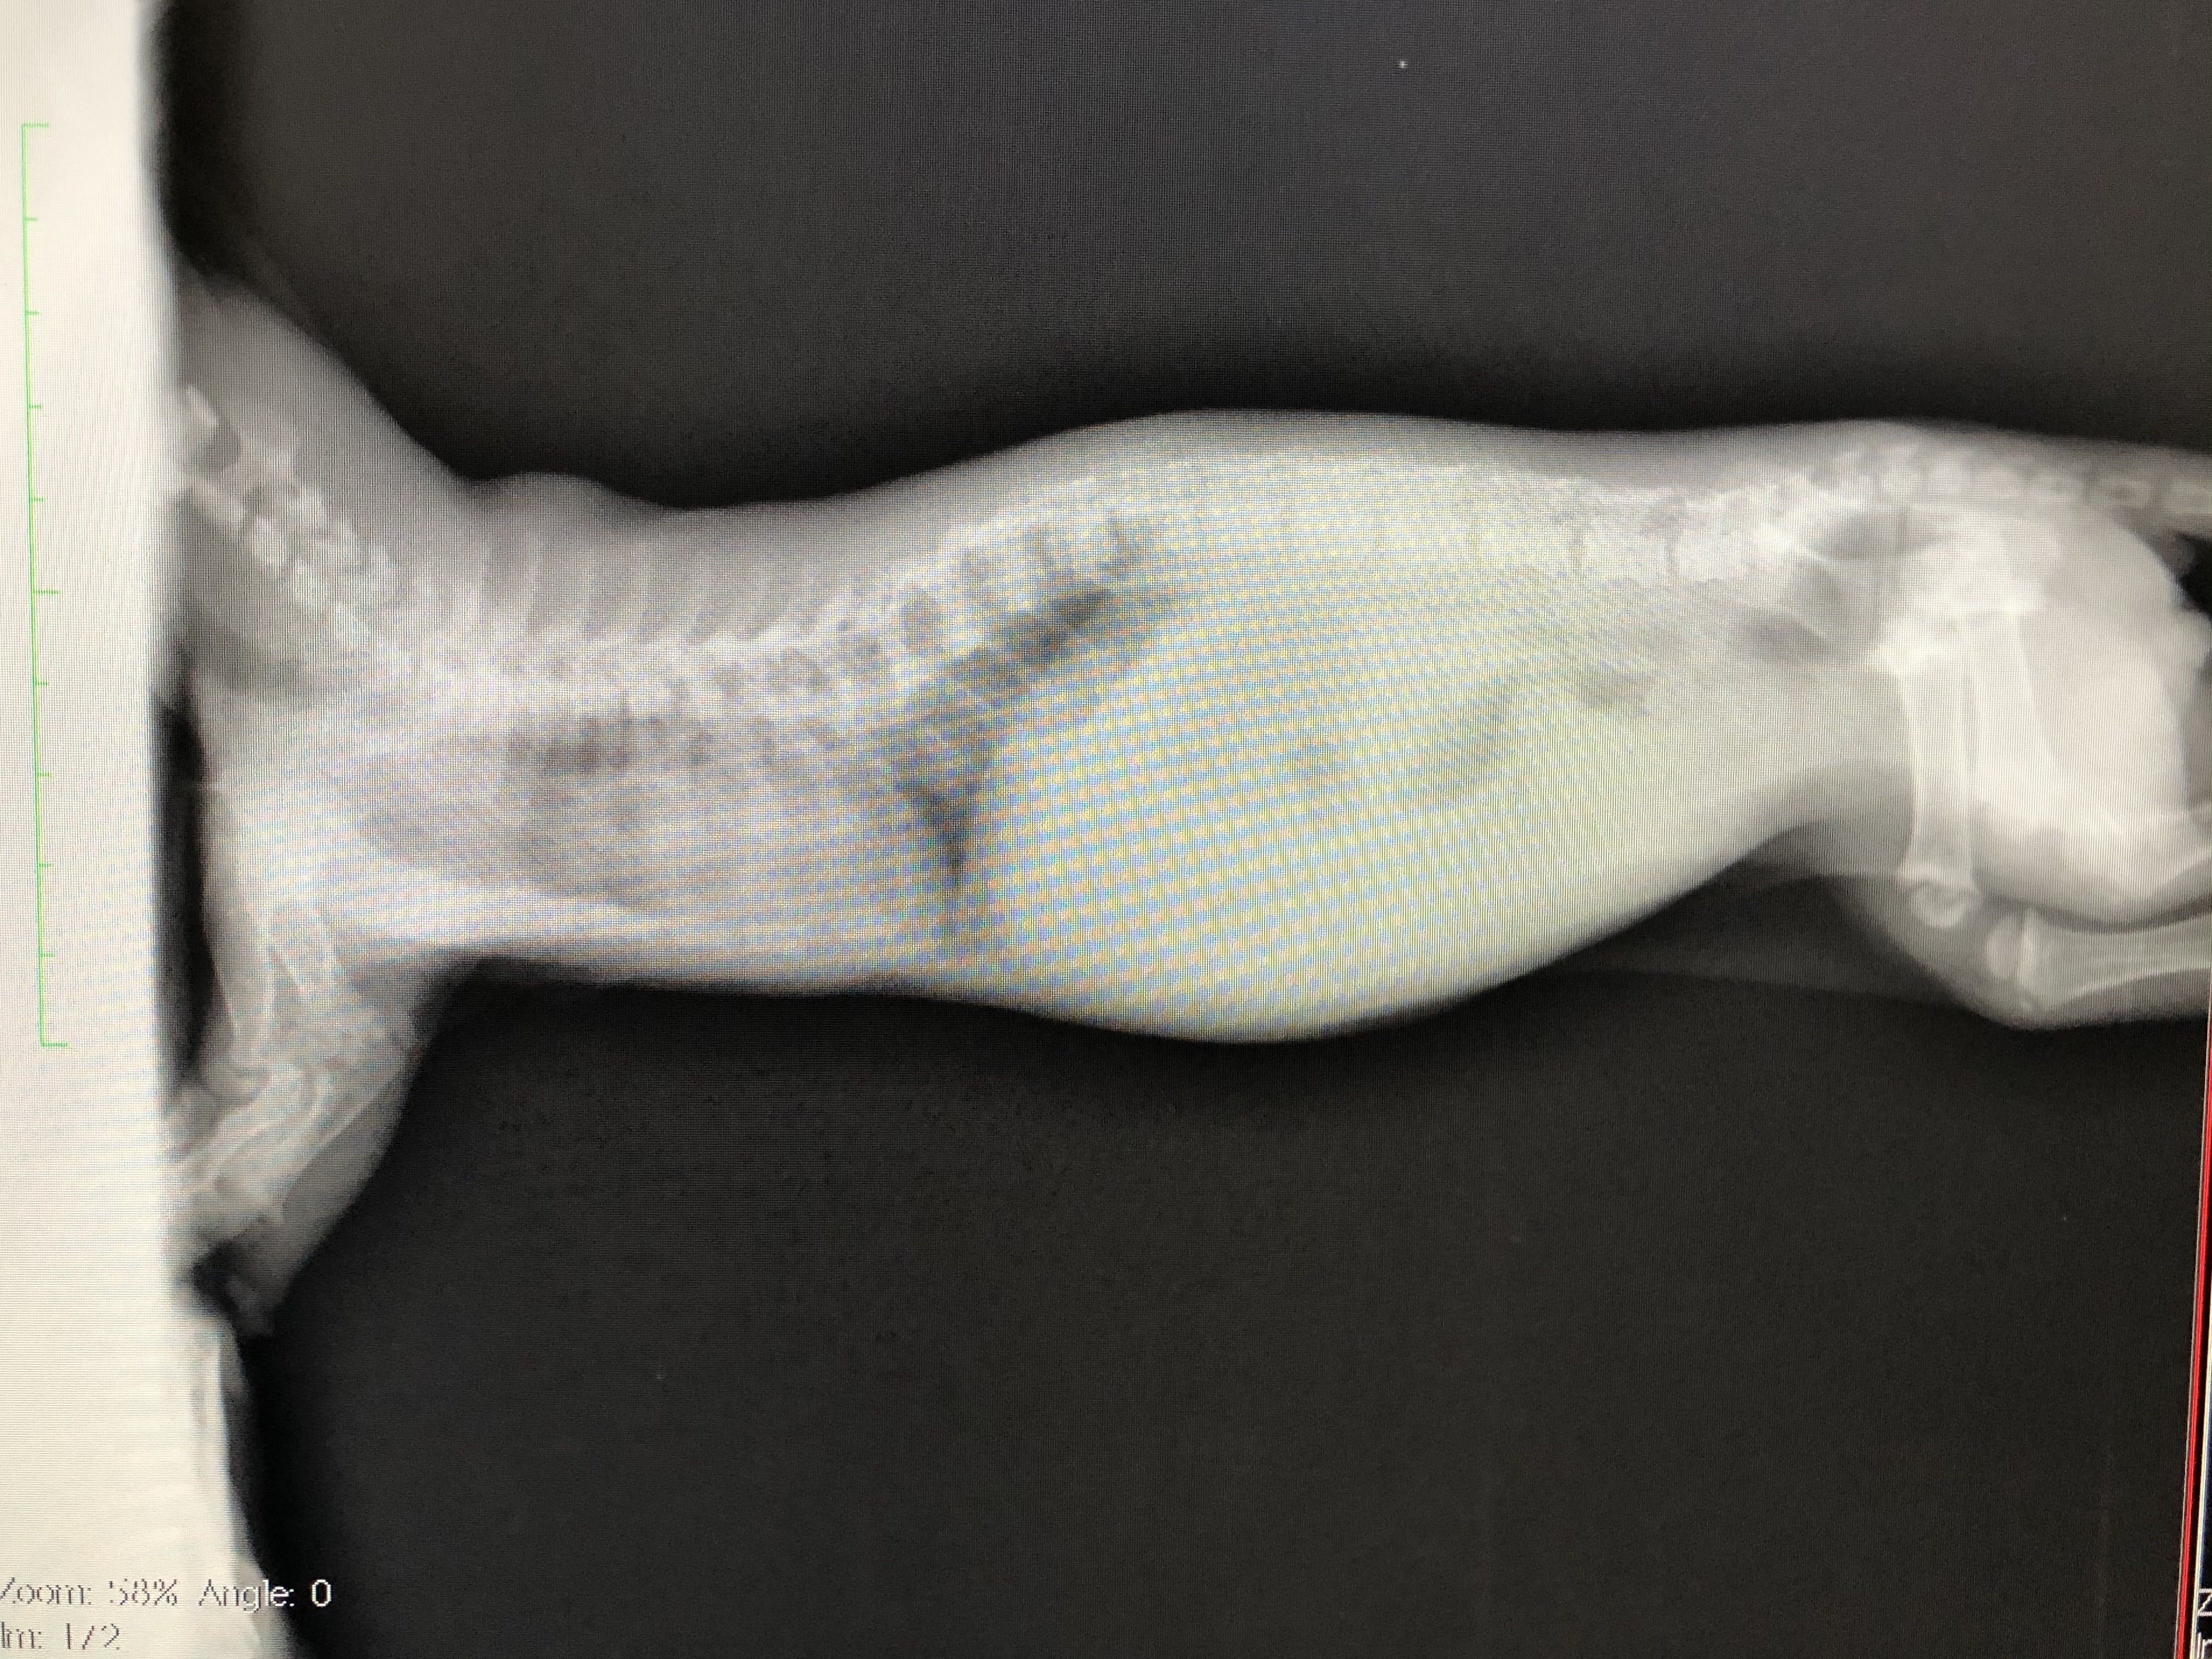

肋骨変形に伴う脊椎側変症

先天的な骨格異常で背骨と肋骨が変形していると診断されました。

また、この骨格異常により、肋骨と背骨の間のスペースが狭く、このまま成長していくと心臓と肺が圧迫され最悪生きられないと言われました。